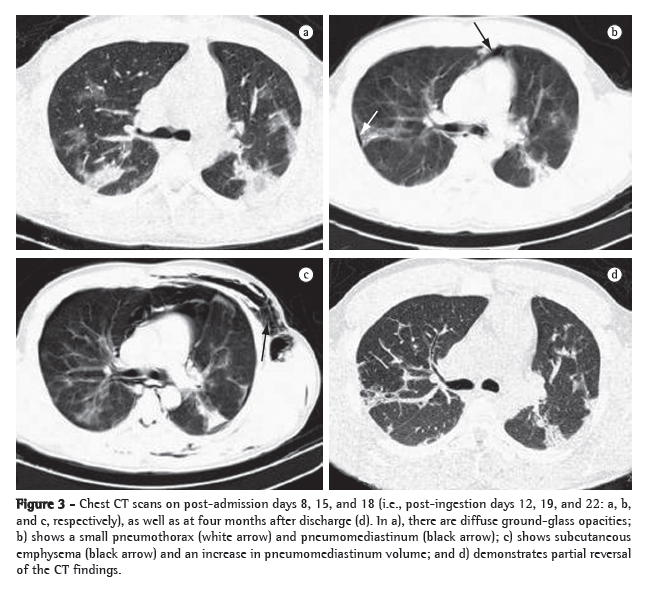

On the second day of hospital admission (post-ingestion day 6), the patient presented hemoptysis. A chest X-ray taken on post-ingestion day 8 showed localized alveolar infiltrate (Figure 2b). Pulmonary opacities, pneumomediastinum, pneumothorax, and subcutaneous emphysema were detected on a chest CT scan (Figure 3). On the seventh day of hospital admission, pulmonary gas exchange parameters worsened (Figure 1), and the patient was submitted to a second course of the same immunosuppressive therapy. Subsequently, despite of an episode of febrile neutropenia, he gradually recovered and was discharged four weeks later in good condition, with no need for home oxygen therapy. Four months later, the patient was working again and had no complaints, except for dyspnea after intense physical exertion. On chest auscultation, crackles were still heard in the lower lung fields, and there was wheezing throughout, together with pleural rub in the right hemithorax. The chest CT scan at four months after discharge is also shown in Figure 3.

The toxicity of paraquat results from the fact that it inhibits the reduction of NADP to NADPH, resulting in the overproduction of reactive oxygen species that destroy the lipids of cell membranes. Consequently, there is inflammation, with leukocyte recruitment and late pulmonary fibrosis, leading to hypoxemia unresponsive to treatment. This physiopathology is usually confirmed by radiological findings,(4)

such as the diffuse ground-glass opacities demonstrated in the present case report.(4) In addition, we observed pneumomediastinum, pneumothorax, and subcutaneous emphysema, which are complications commonly ascribed to the pulmonary toxicity of paraquat.(5)